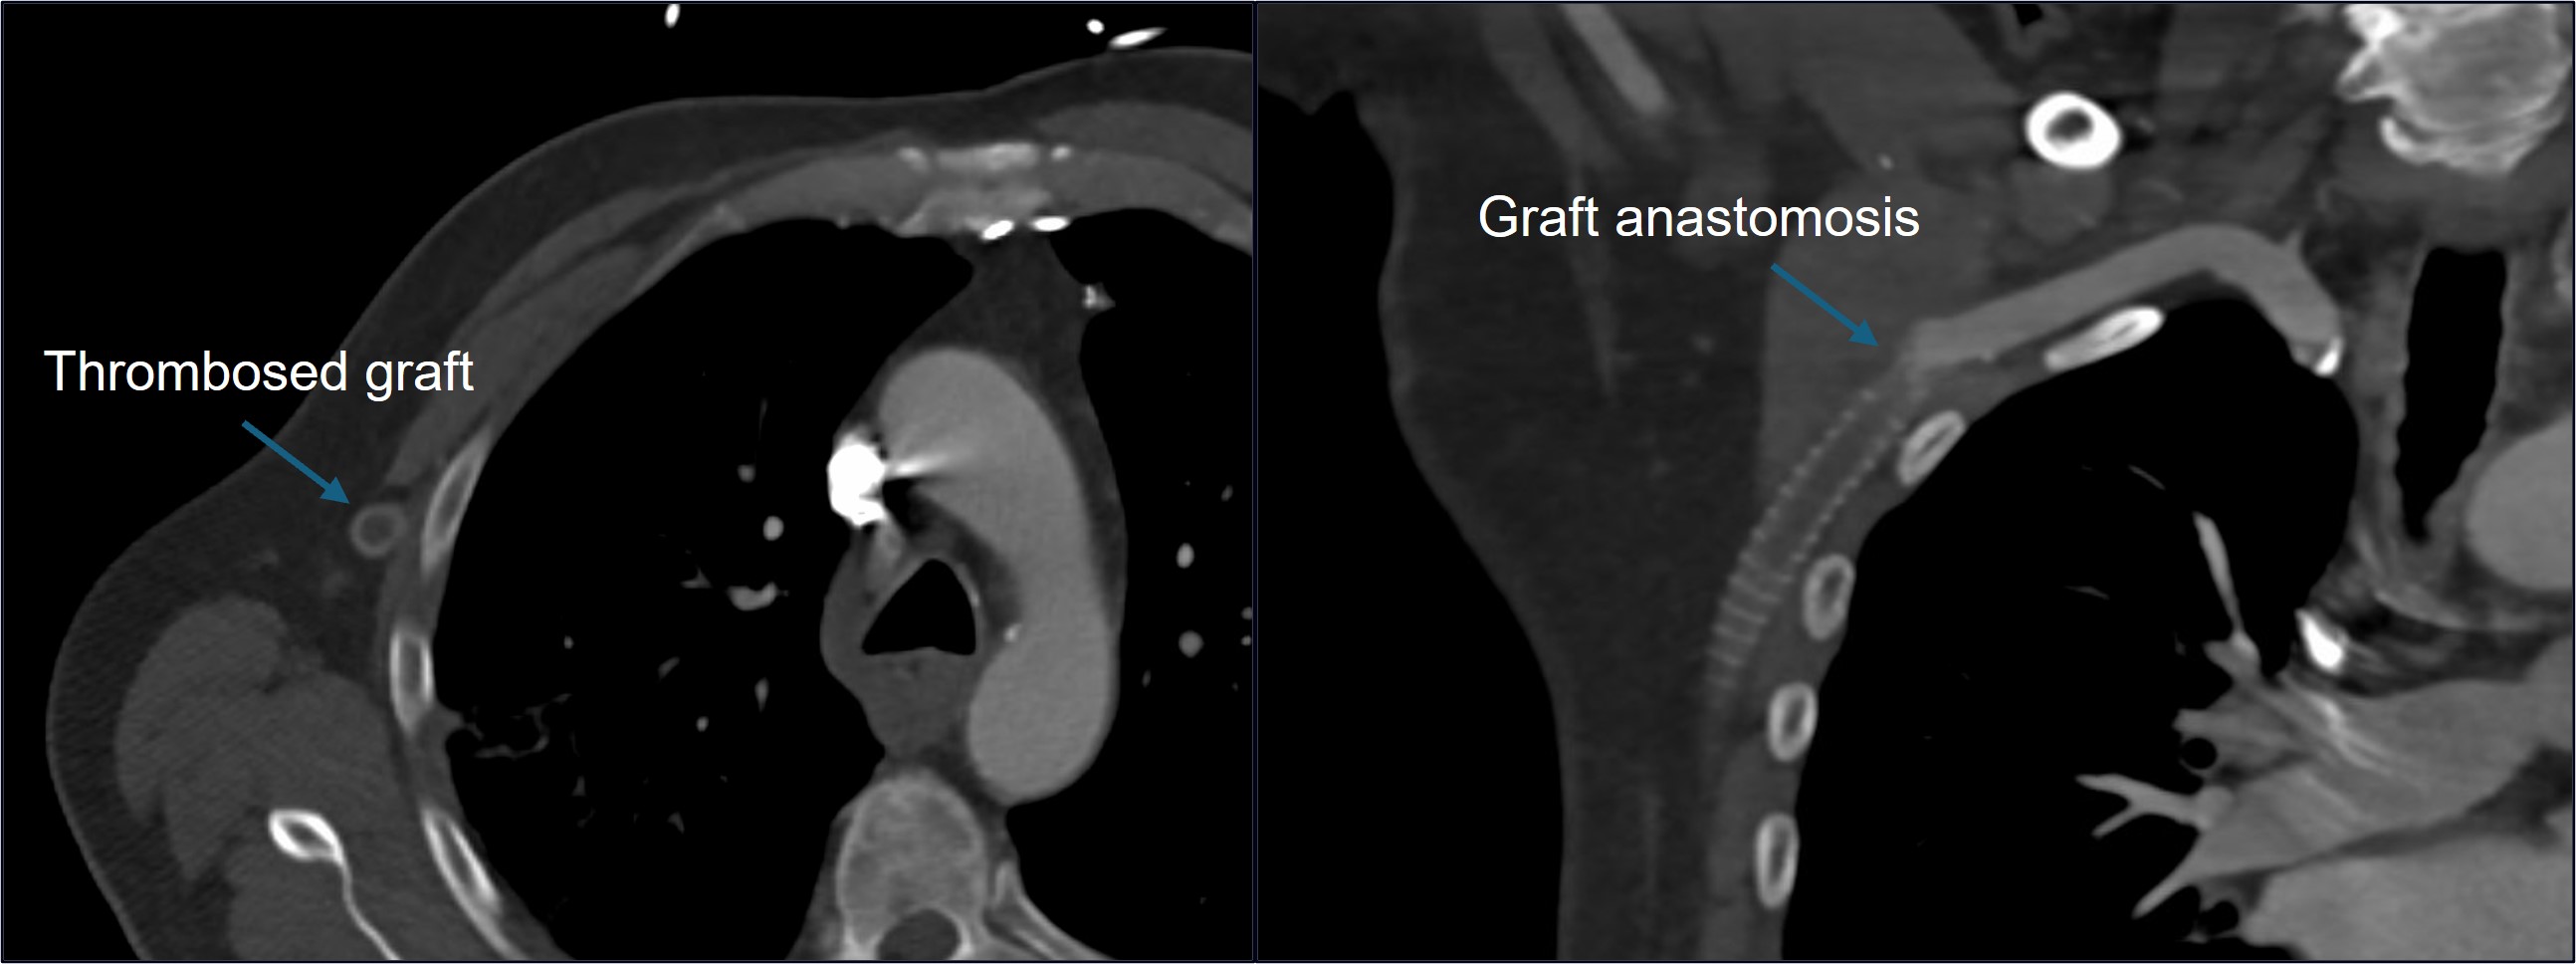

A 63-year-old male with PAD presented with right leg pain, claudication, and paresthesia in his foot. The patient also reported right ankle pain and a burning sensation in his right thigh one month prior. His history included an occluded right iliac stent, a failed right iliofemoral bypass graft, right common femoral endartectomy and profundoplasty, failed right femoral-popliteal bypass graft, and a right axillary-profunda bypass graft placed two years prior due to a hostile groin after femoral-popliteal graft infection. Computed tomography angiography showed a completely thrombosed axillary-profunda graft (Figure 1). A decision was made to revascularize the axillary-profunda graft using Artix followed by profundoplasty.